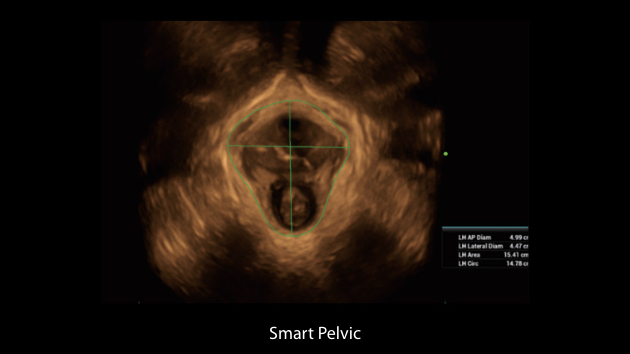

Nuewa I9? ??? ???? ?? ??? ?? ??? ???? ?? ??? ???? ???? ??? ?????. ??? ??? ??? ?? ????? ?? ???? ???? ???? ???? ??? ???? ??? ??? ???? ??? ???? ??? ?? ?????.

ZST+ ???? ???? ??? ???? ??? ?????. ??? ????? ??? ? ???? ?? ??? ?? ????? ?????. ?? ???, ?? ???, ?? ??? ?? ?? ?? ??? ??? ???? ???? ??? ?? ??? ?? ???? ?? ??? ?? ??? ?????.